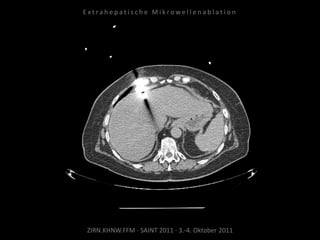

Ablation am 17.08.2010

Metastase lateral der linken Niere:

1 Nadelposition.

Metastase medial des linken

Musculus iliacus: